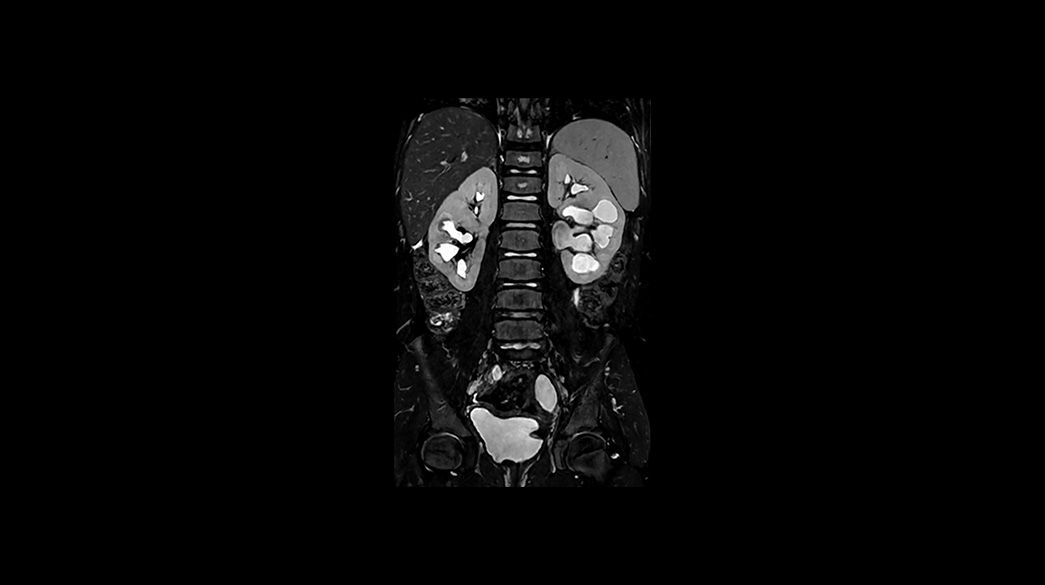

LAVA1040-x-585

DISCO-and-DISCO-Flex1040-x-585

Read case study